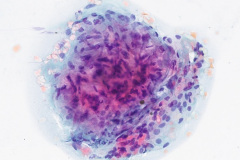

Cytologic Diagnosis: Negative for malignant cells, acute inflammation, multinucleated giant cells, few poorly formed granulomas, iron pill fragments.

Cytology:

Initial diagnosis of IPA is not always readily distinguishable on cytology examination of slides. There may be a presence of a small amount of yellow-brown material on modified Romanowsky and Papanicolaou stains which without the clinical history of aspiration could easily be interpreted as non-specific artifact or other types of pigmented particles such as hemosiderin or carbonaceous particles.6 Histological examination of biopsy material is typically the gold standard for diagnosis, wherein iron pill injury is characterized by the presence of crystalline iron fibrils in the presence of necrosis or in an ulcer base.1 An iron stain such as Perls’ Prussian Blue can aid in determining the iron composition of the yellow-brown material by staining iron as a bright blue color.9 Microscopic features of the biological response to the aspiration exposure may include the presence of multinucleated giant cells, hemosiderin-laden macrophages, granulomas, and reactive atypia of squamous metaplasia. Care should be taken when assessing the Prussian Blue stain results as the hemosiderin in macrophages will also stain positively.9

Sarcoidosis – Pulmonary sarcoidosis presents in a wide variety of clinical conditions from an asymptomatic state to a severe pulmonary disorder which can lead to respiratory failure. The symptoms of pulmonary sarcoidosis are nonspecific and typically include dyspnea and cough. Bilateral hilar adenopathy is observed in 50 – 85% and parenchymal opacities in 20 – 65% of cases.12 Since there is no known cause and no definitive biomarkers, diagnosis of pulmonary sarcoidosis relies on the presence of non-necrotizing granulomatous inflammation in the involved tissue with the exclusion of alternative granulomatous diseases.12 The non-necrotizing granulomas of pulmonary sarcoidosis appear histologically as discrete, well-circumscribed aggregates of epithelial cells, macrophages, multinucleated giant cells and CD4+ T lymphocytes.12